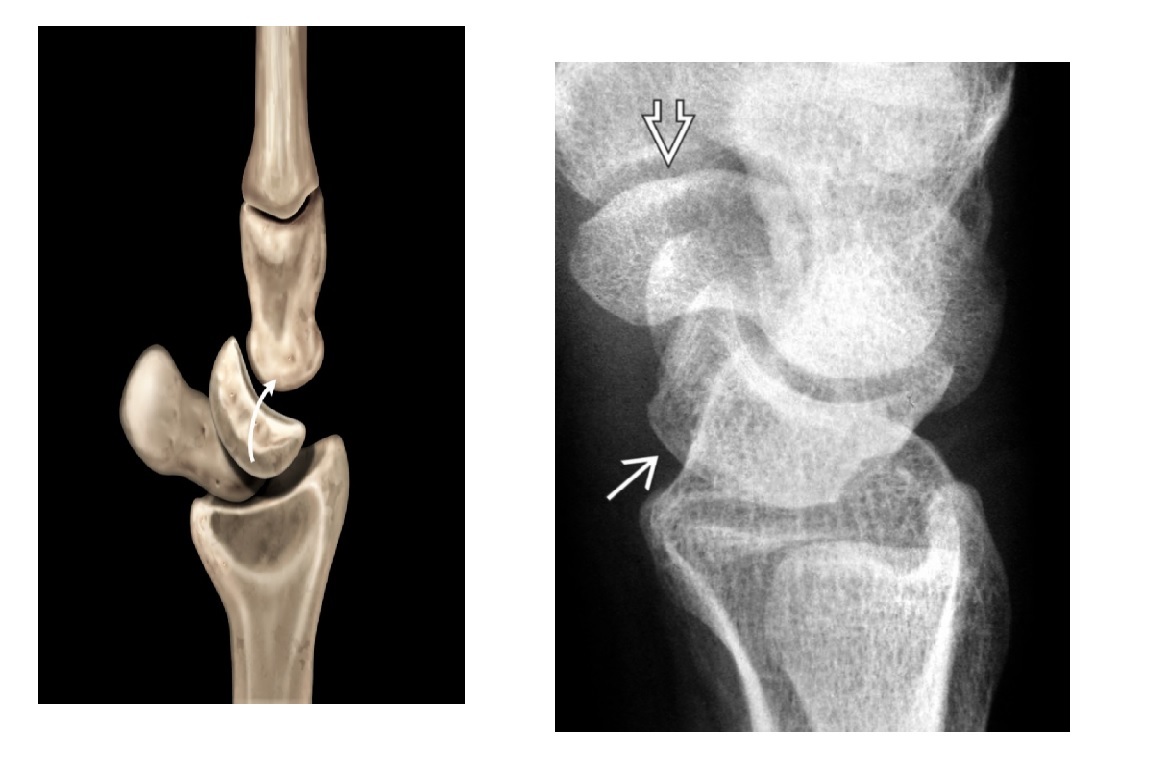

Segond fracture

Lateral tibial plateau

Associated with ACL tear (75%) and internal rotation

MR SL = Medial Reverse Lateral Segond